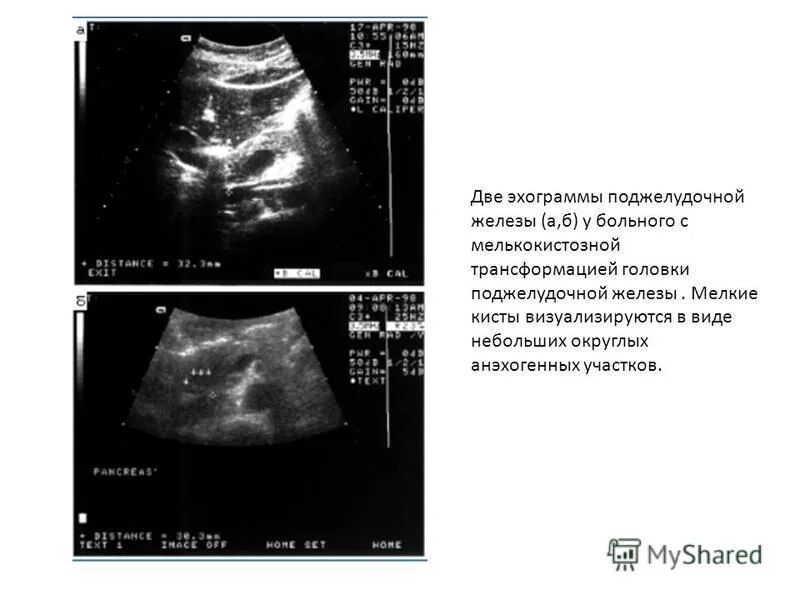

Диффузные изменения киста поджелудочной железы